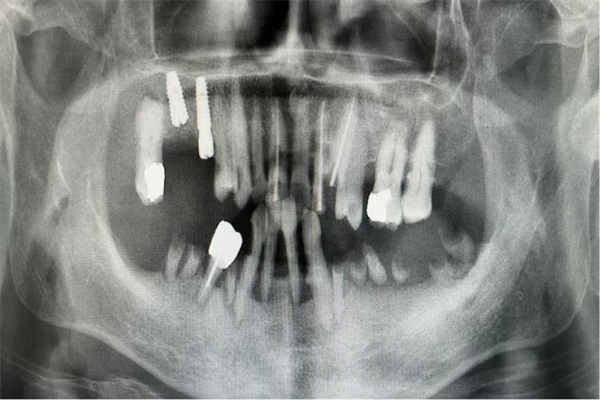

術(shù)前曲面斷層片檢查

接診后,王可醫(yī)生認(rèn)真聽取了阿姨的訴求,并與楊濤主任一同對阿姨的病情進(jìn)行了分析討論。經(jīng)過與家屬充分溝通并征得同意后,決定對阿姨實施拔除松動殘根后即刻行數(shù)字化全口種植牙術(shù),術(shù)后即刻行過渡義齒修復(fù),降低等待期間缺牙對美觀及咀嚼功能的影響。

術(shù)前,楊濤主任與王可醫(yī)生對阿姨擬種植區(qū)牙體、牙周狀況、牙槽骨、咬合關(guān)系、全身健康狀況等進(jìn)行了精細(xì)的檢查與評估,并定制了數(shù)字化導(dǎo)板。